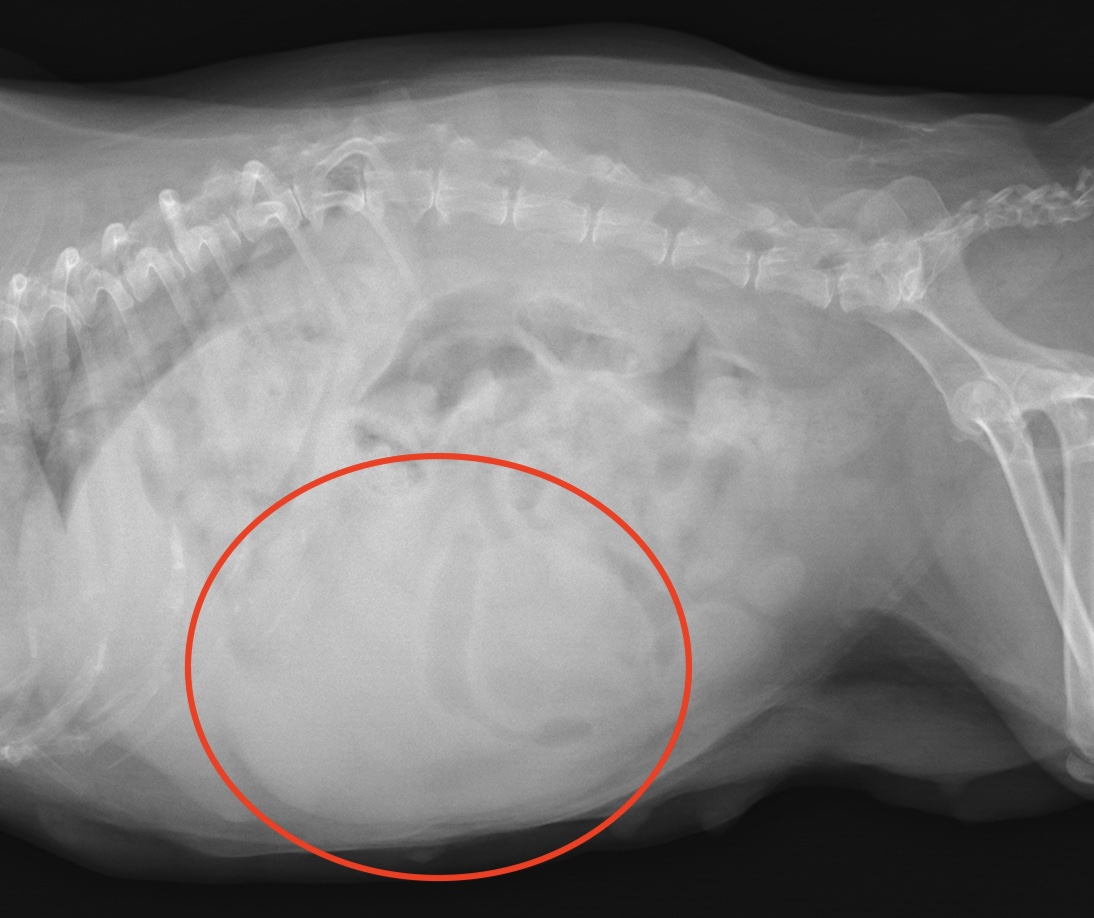

・レントゲン検査:がんの大きさ、遠隔転移(肺など)の評価

肝細胞癌のレントゲン画像(赤丸)